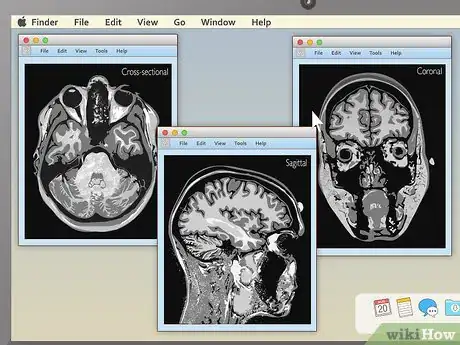

1Familiarize yourself with the different MRI viewing schemes. When your MRI first loads up, if you're lucky, it will be immediately obvious what you're looking at. However, in many cases, the image you see may be a completely unintelligible mix of black, white, and grey. Knowing how MRIs are shot can help you make sense of your images. The three main ways MRIs are displayed are:[4]

- Sagittal: Often the easiest for non-doctors to interpret. Sagittal MRIs are basically side or profile views of your body. The image is as if you've been sliced in half vertically, from your head to your pelvis.

- Coronal: These images are basically a "head on" view of your body. You're looking at your features vertically from the front — as if you were standing facing the camera.

- Cross-sectional: Often the hardest for non-doctors to interpret. Here, you're basically viewing thin slices of your body from the top down — as if you've been cut into many thin horizontal slices from your head to your toes like a salami.